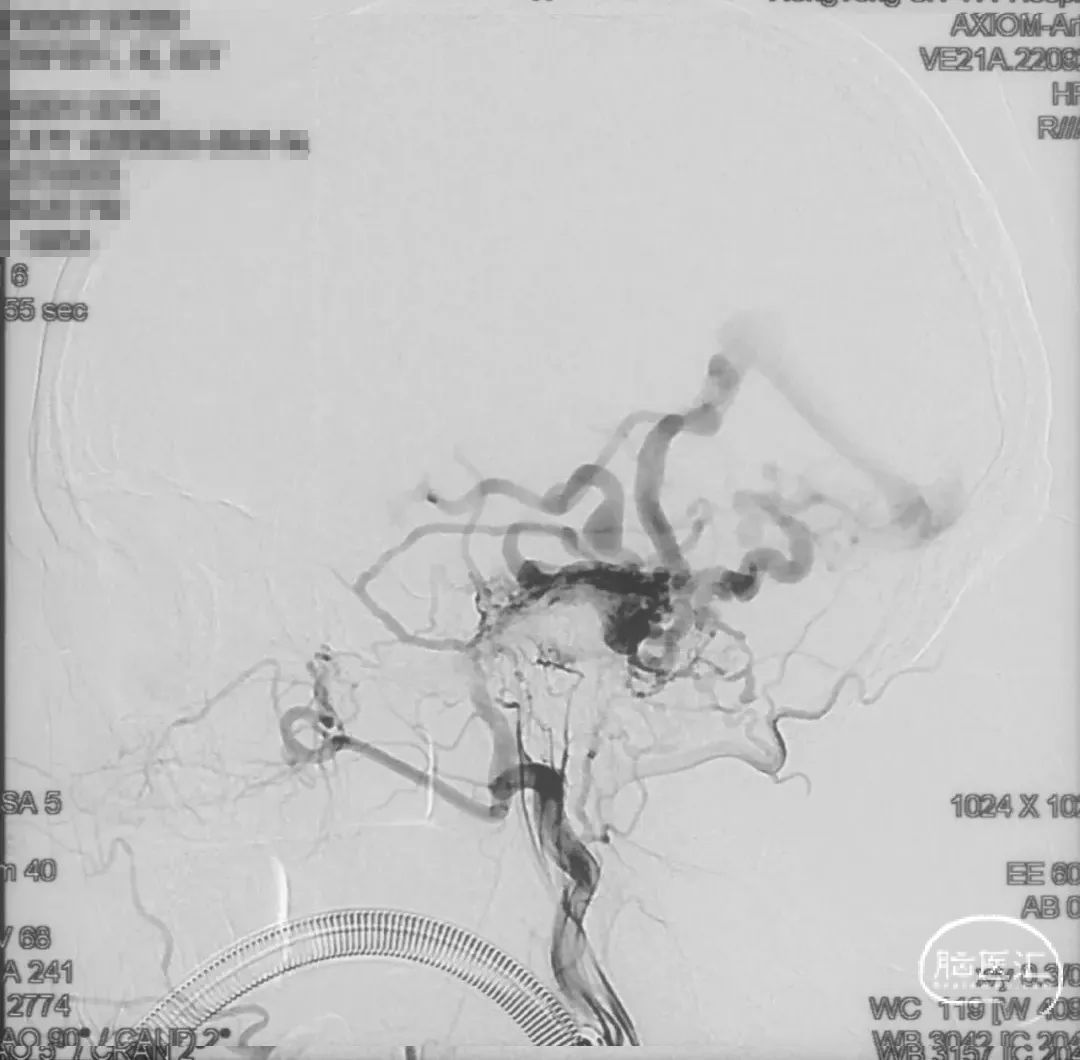

术前造影

证实为TDAVF,为岩上窦型。R-ECA正侧位见右侧脑膜中动脉分支、枕动脉分支、颞浅动脉分支向瘘口供血,经幕上迂曲扩张的静脉、中脑周围静脉、基底静脉向深部静脉引流。

R-ICA正侧位见右侧脑膜垂体干向瘘口供血

L-ICA正侧位见左侧脑膜垂体干分支向瘘口供血

L-ECA正侧位未见向瘘口供血

L-VA、R-VA正侧位右侧小脑上动脉脑膜支向瘘口供血

结构分析:右侧天幕区硬脑膜动静脉瘘,瘘口位于右侧岩上窦,供血动脉主要包括右侧脑膜中动脉的颞支、岩鳞支,右侧枕动脉分支,右侧颞浅动脉分支,双侧脑膜垂体干,右侧小脑上动脉脑膜支,经幕上迂曲扩张的静脉、中脑周围静脉、基底静脉向深部静脉引流,引流静脉起始部见扩张的静脉球。Cognard分型IV型,Borden分型III型,Lawton分型IV型(岩上窦型)。